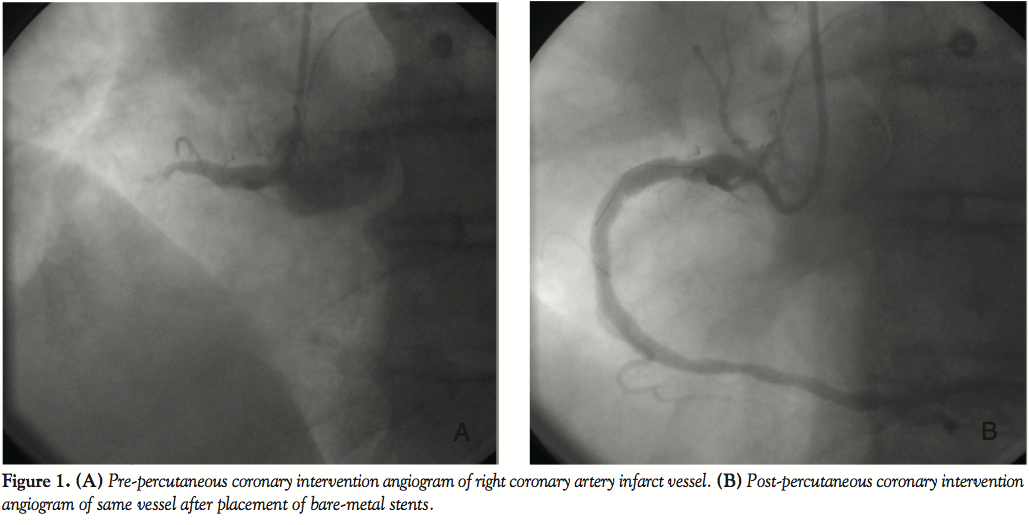

On day 3, the patient was brought back to the cath lab for staged PCI. An 8 French (Fr) Amplatz™ Left (AL) 2.0 guide (Boston Scientific, Natick, Massachusetts) was selected for increased support, and a Whisper™ wire (Abbott Vascular, Abbott Park, Illinois) was advanced easily through the lesion. Due to the lesion proximity to a large ramus intermedius bifurcation, a BMW™ wire (Abbott Vascular) was placed in the ramus for protection from potential plaque shift. A 3.0 x 20 mm Voyager™ NC noncompliant balloon (Abbott Vascular) was used for predilation, inflated at 14 atm for 30 seconds, to apparent full expansion. A Cypher sirolimus-eluting stent (on Bx Velocity™ platform [Cordis Corporation, Miami Lakes, Florida) was requested, but was not stocked in the 3.5 x 23 mm size that was required. Thus, a 4.0 x 24 mm Taxus paclitaxel-eluting stent (on Liberte™ platform [Boston Scientfic]) was chosen, deployed at 16 atm for 30 seconds. Postdeployment cineangiography appeared to demonstrate full expansion of the stent within the target stenosis (Figure 3A). However, when attempts were then made to withdraw the balloon into the guide, it would not disengage from the stent scaffolding.

Subsequent views with the balloon in place revealed no-reflow distal to the stent (Figure 3B). A number of techniques were applied in attempts to free the balloon (see discussion below), but were proven unsuccessful. Ultimately, after all other percutaneous options to disengage the balloon were exhausted, the surgical backup team was alerted, and the patient was accepted for an emergent CABG. The patient was transferred directly to the surgical suite, where he underwent LAD bypass. Coronary arteriotomy at the level of the balloon and stent was performed, the balloon catheter and stent were removed, and a vein patch was applied. The stent and balloon were quite deformed (Figure 4). The postoperative course was uneventful, and the patient was discharged on postop day 13.